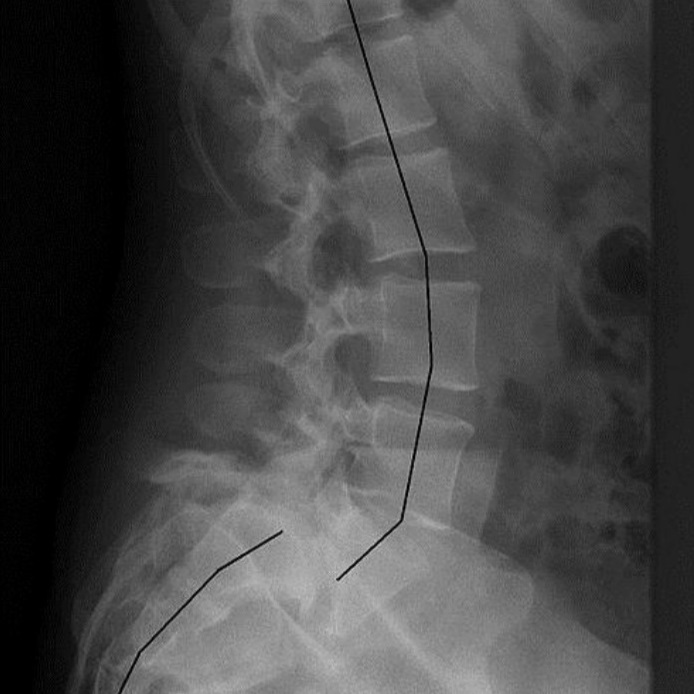

Kręgozmyk, znany również jako spondylolisteza, to stan, w którym jeden kręg przesuwa się w stosunku do drugiego, najczęściej do przodu. Może to prowadzić do bólu, ograniczenia ruchomości oraz innych poważnych problemów zdrowotnych. Kręgozmyk najczęściej dotyczy odcinka lędźwiowo-krzyżowego kręgosłupa, ale może występować również w innych jego częściach.

Stopnie zaawansowania kręgozmyku określa się na podstawie procentowego przemieszczenia kręgu górnego nad dolnym kręgiem, wg skali Meyerdinga:

- Stopień I: Przesunięcie mniejsze niż 25%.

- Stopień II: Przesunięcie w granicach 25-50%.

- Stopień III: Przesunięcie w granicach 50-75%.

- Stopień IV: Przesunięcie powyżej 75%.

- Stopień V (spondylolisteza całkowita): Utrata styczności kręgów.

- RTG (rentgen): Podstawowe badanie obrazowe, które pozwala zobaczyć przemieszczenie kręgów.